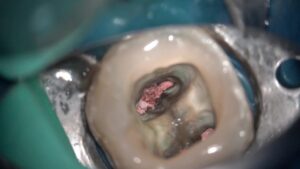

マイクロスコープラバーダム防湿福岡・大濠公園・歯医者精密歯科治療・マイクロスコープ皆さんこんにちは辻本デンタルオフィス院長の辻本です。普段当院で行っているマイクロスコープを使用した根管治療は肉眼での治療では行うことが困難な細部まできれいにすることで病気の再発や、失敗を避けることが出来ます。 今回は歯の根の間、股の部分(根分岐部)に大きな病気が出来ていた歯の治療の動画を見ていただきたいと思います。 治療から約3年半経過しておりますが、問題なく経過しています。根管治療でお困りの方は一度辻本デンタルオフィスへご相談ください。...